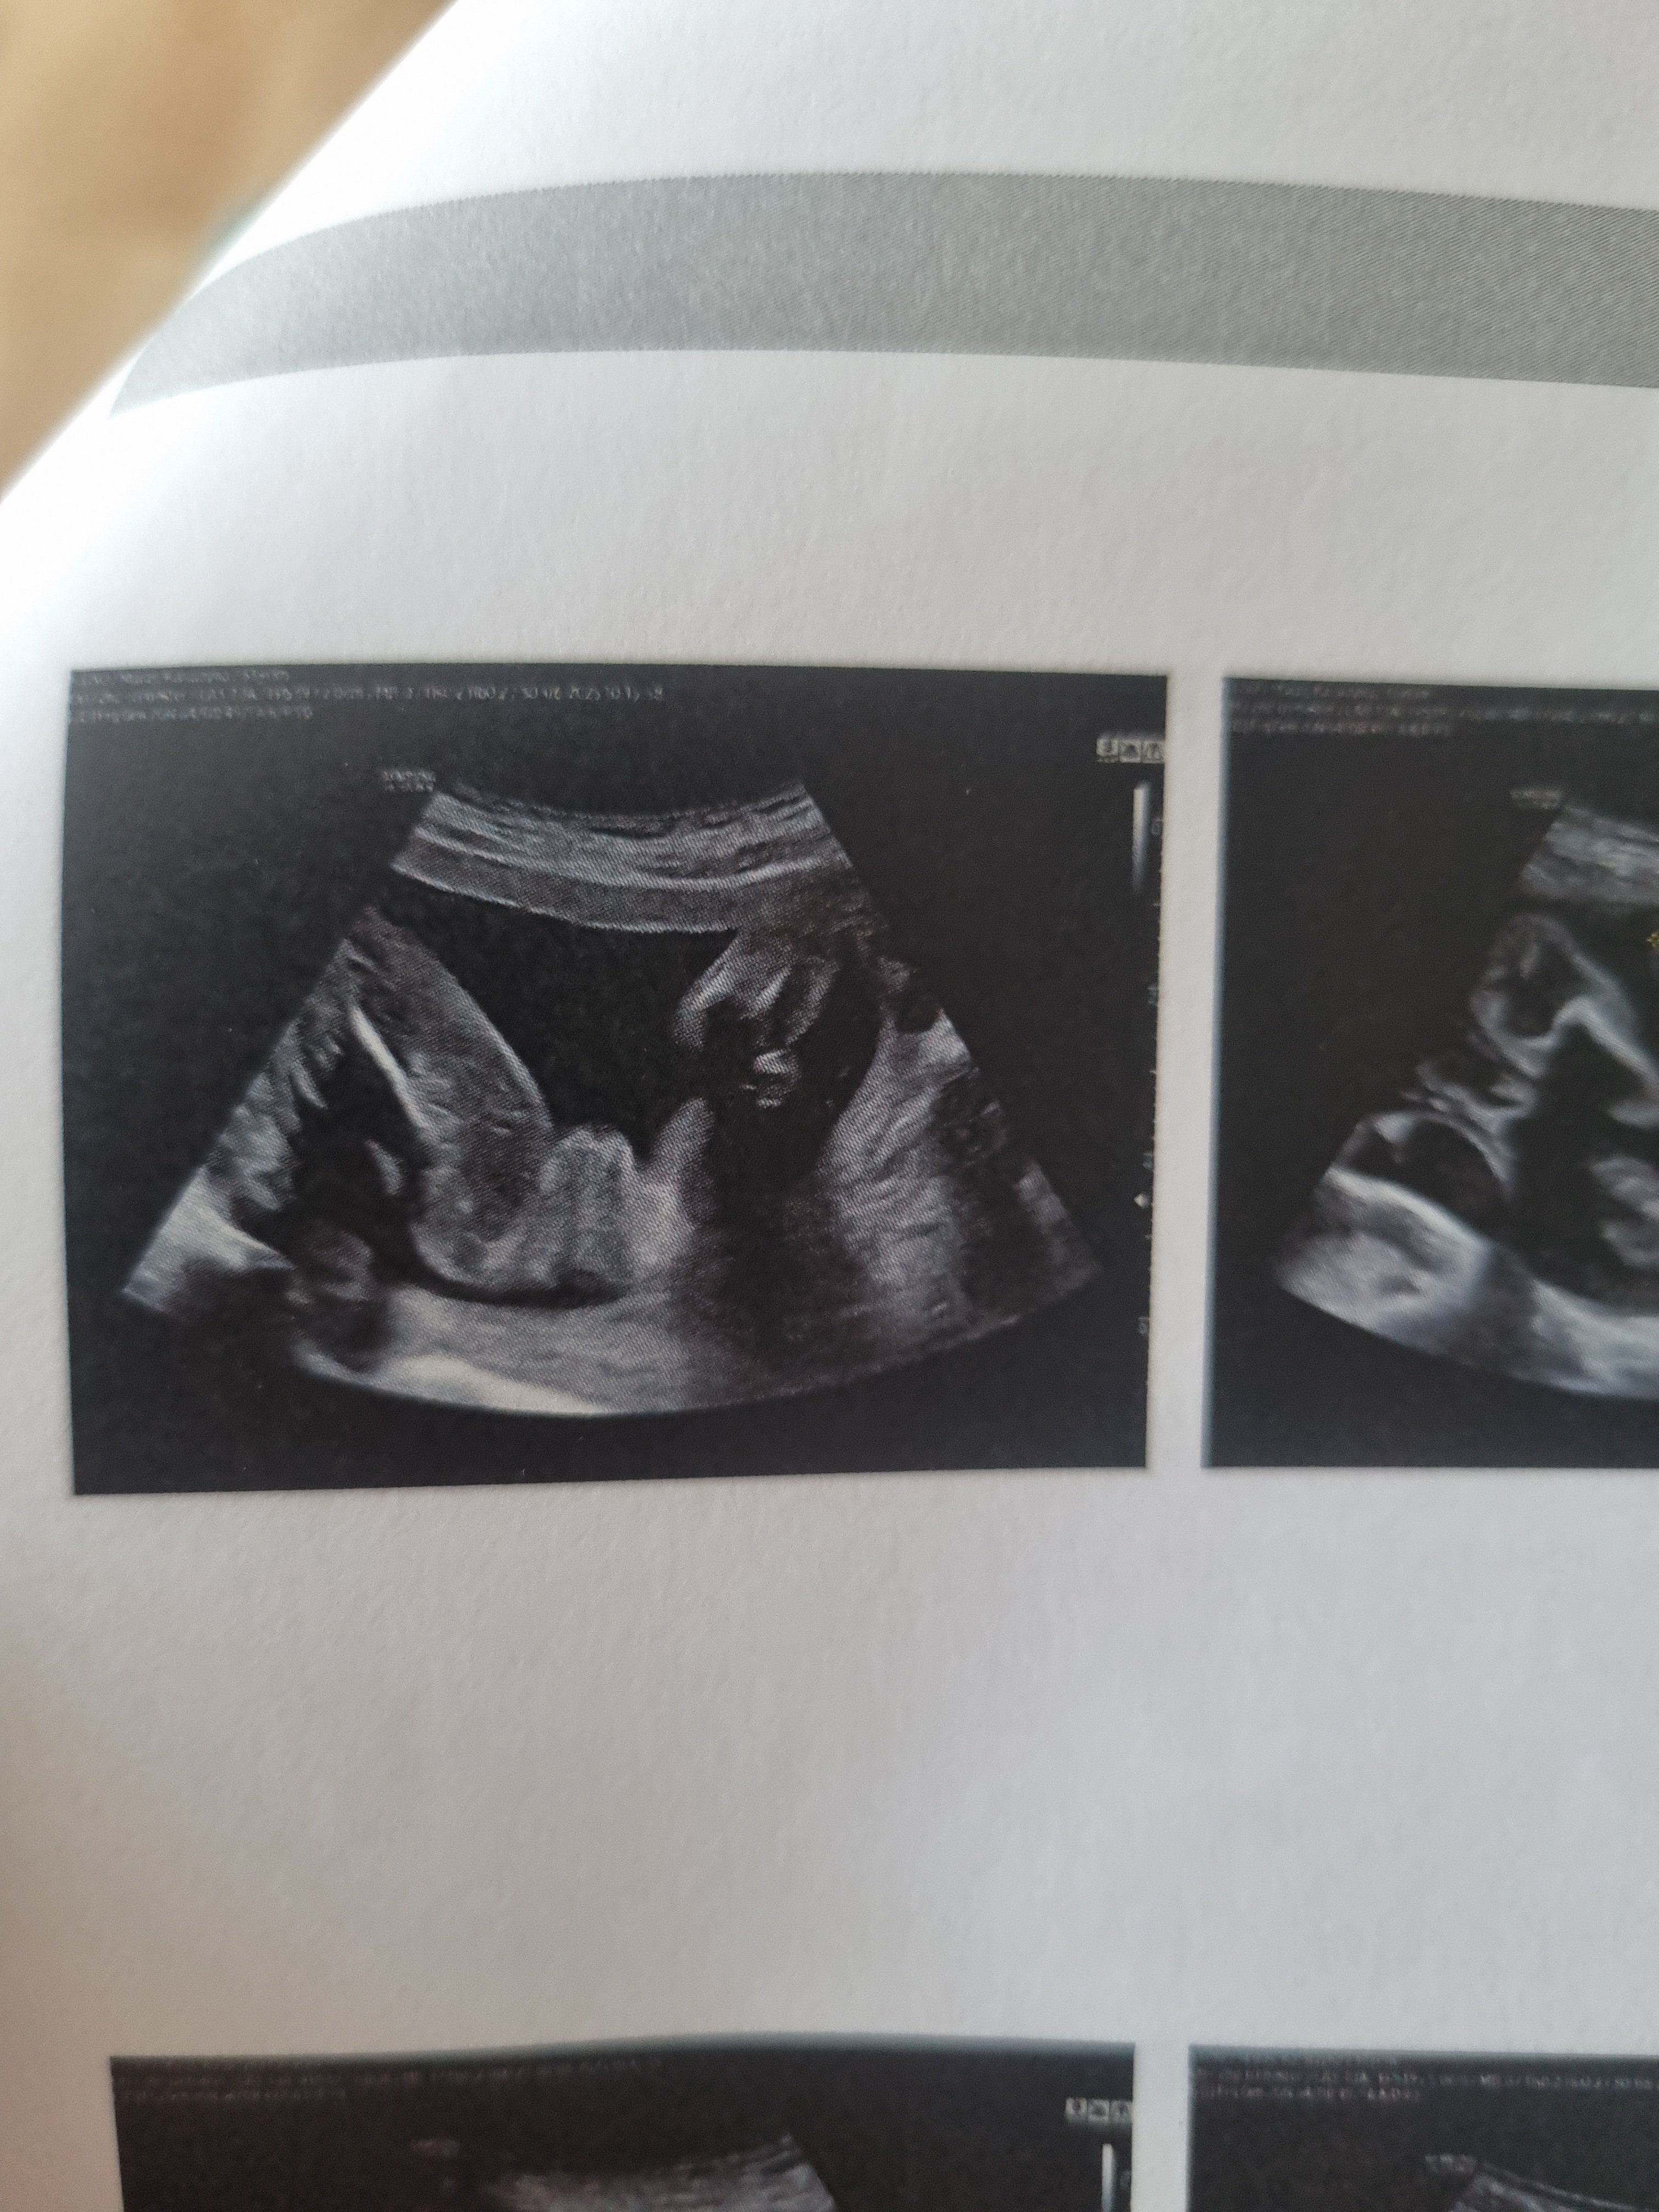

Płeć dziecka USG

Czy po tym zdjęciu widać jaka płeć maluszka?

Jestem w 12 tygodniu ciąży :) czy za wcześnie